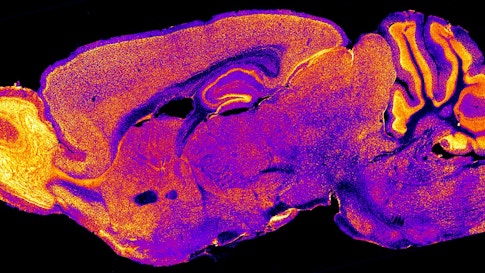

SHANK3 is one of many genes involved in the formation of synapses, the junctions between neurons that allow them to send signals to each other. In mice lacking SHANK3, neurons in a brain region called the striatum communicate at synapses less effectively than do those of control mice. But turning the gene on in adulthood reverses this deficit and also rescues the mice’s obsessive grooming and social deficits, the researchers reported February 25, 2016, in Nature.